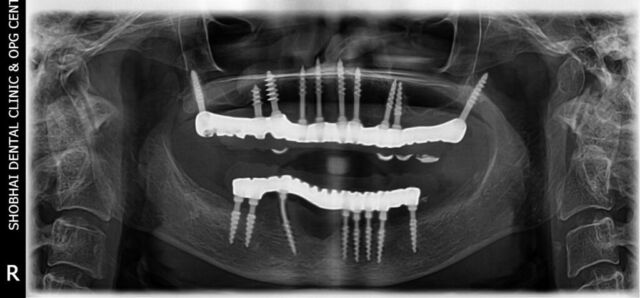

We offer all types of dental treatments at our dental clinic including basic and advanced treatments like full mouth dental implants.